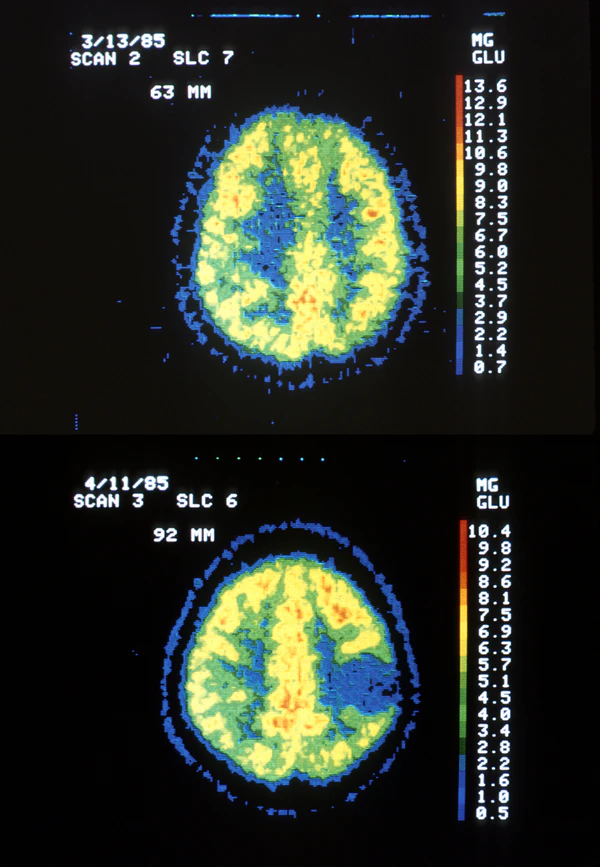

Магнитно-резонансная томография головного мозга: высокозлокачественные астроцитомы при стандартном исследовании характеризуются выраженным контрастным усилением, перитуморальным отёком (видимым в режиме Т2 с подавлением сигнала от жидкости), объёмным воздействием, неоднородностью структуры, центральным некрозом и внутриопухолевыми кровоизлияниями. Астроцитомы низкой степени злокачественности обычно представлены хорошо отграниченными однородными образованиями с минимальным или отсутствующим объёмным эффектом, отёком и контрастным усилением. Для опухолей низкой степени злокачественности характерны высокий коэффициент диффузии, низкий относительный церебральный объём крови и низкие соотношения холина и липид-лактата к креатину; для опухолей высокой степени злокачественности — противоположные изменения[4].